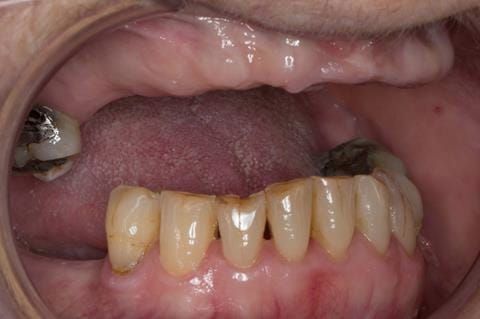

- Poorly fitting cobalt chromium based maxillary partial denture, which has been added to. This exhibited poor retention, stability and tissue fit (support). Unable to wear a new acrylic based denture.

- UR7 - occlusal amalgam. 10- 20% alveolar bone loss. Healthy periodontium with reduced attachment level. No mobility.

- Eight mandibular anterior teeth worn incisal edges from now extracted maxillary anterior crowns. Gingivitis - owing to inadequate oral hygiene.

- LL6 with large amalgam restoration - healthy periodontium.

- Bruxism.